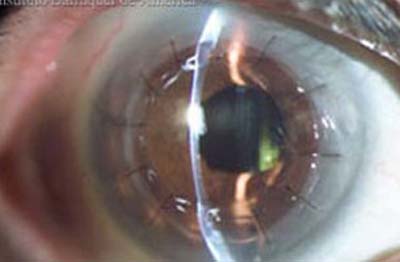

Queratoplastia de Espesor Total o Penetrante.

Se realiza cuando todas las capas de la córnea están comprometidas. El diámetro de los injertos oscila entre 7.0 y 9.0 mm según el área de compromiso corneal. Se sutura con puntos separados borde a borde o con sutura continua de poliamidas (Nylon). La cicatrización es lenta y los puntos se retiran entre los 6 y los 12 meses de post-operatorio.

Queratoplastia Penetrante